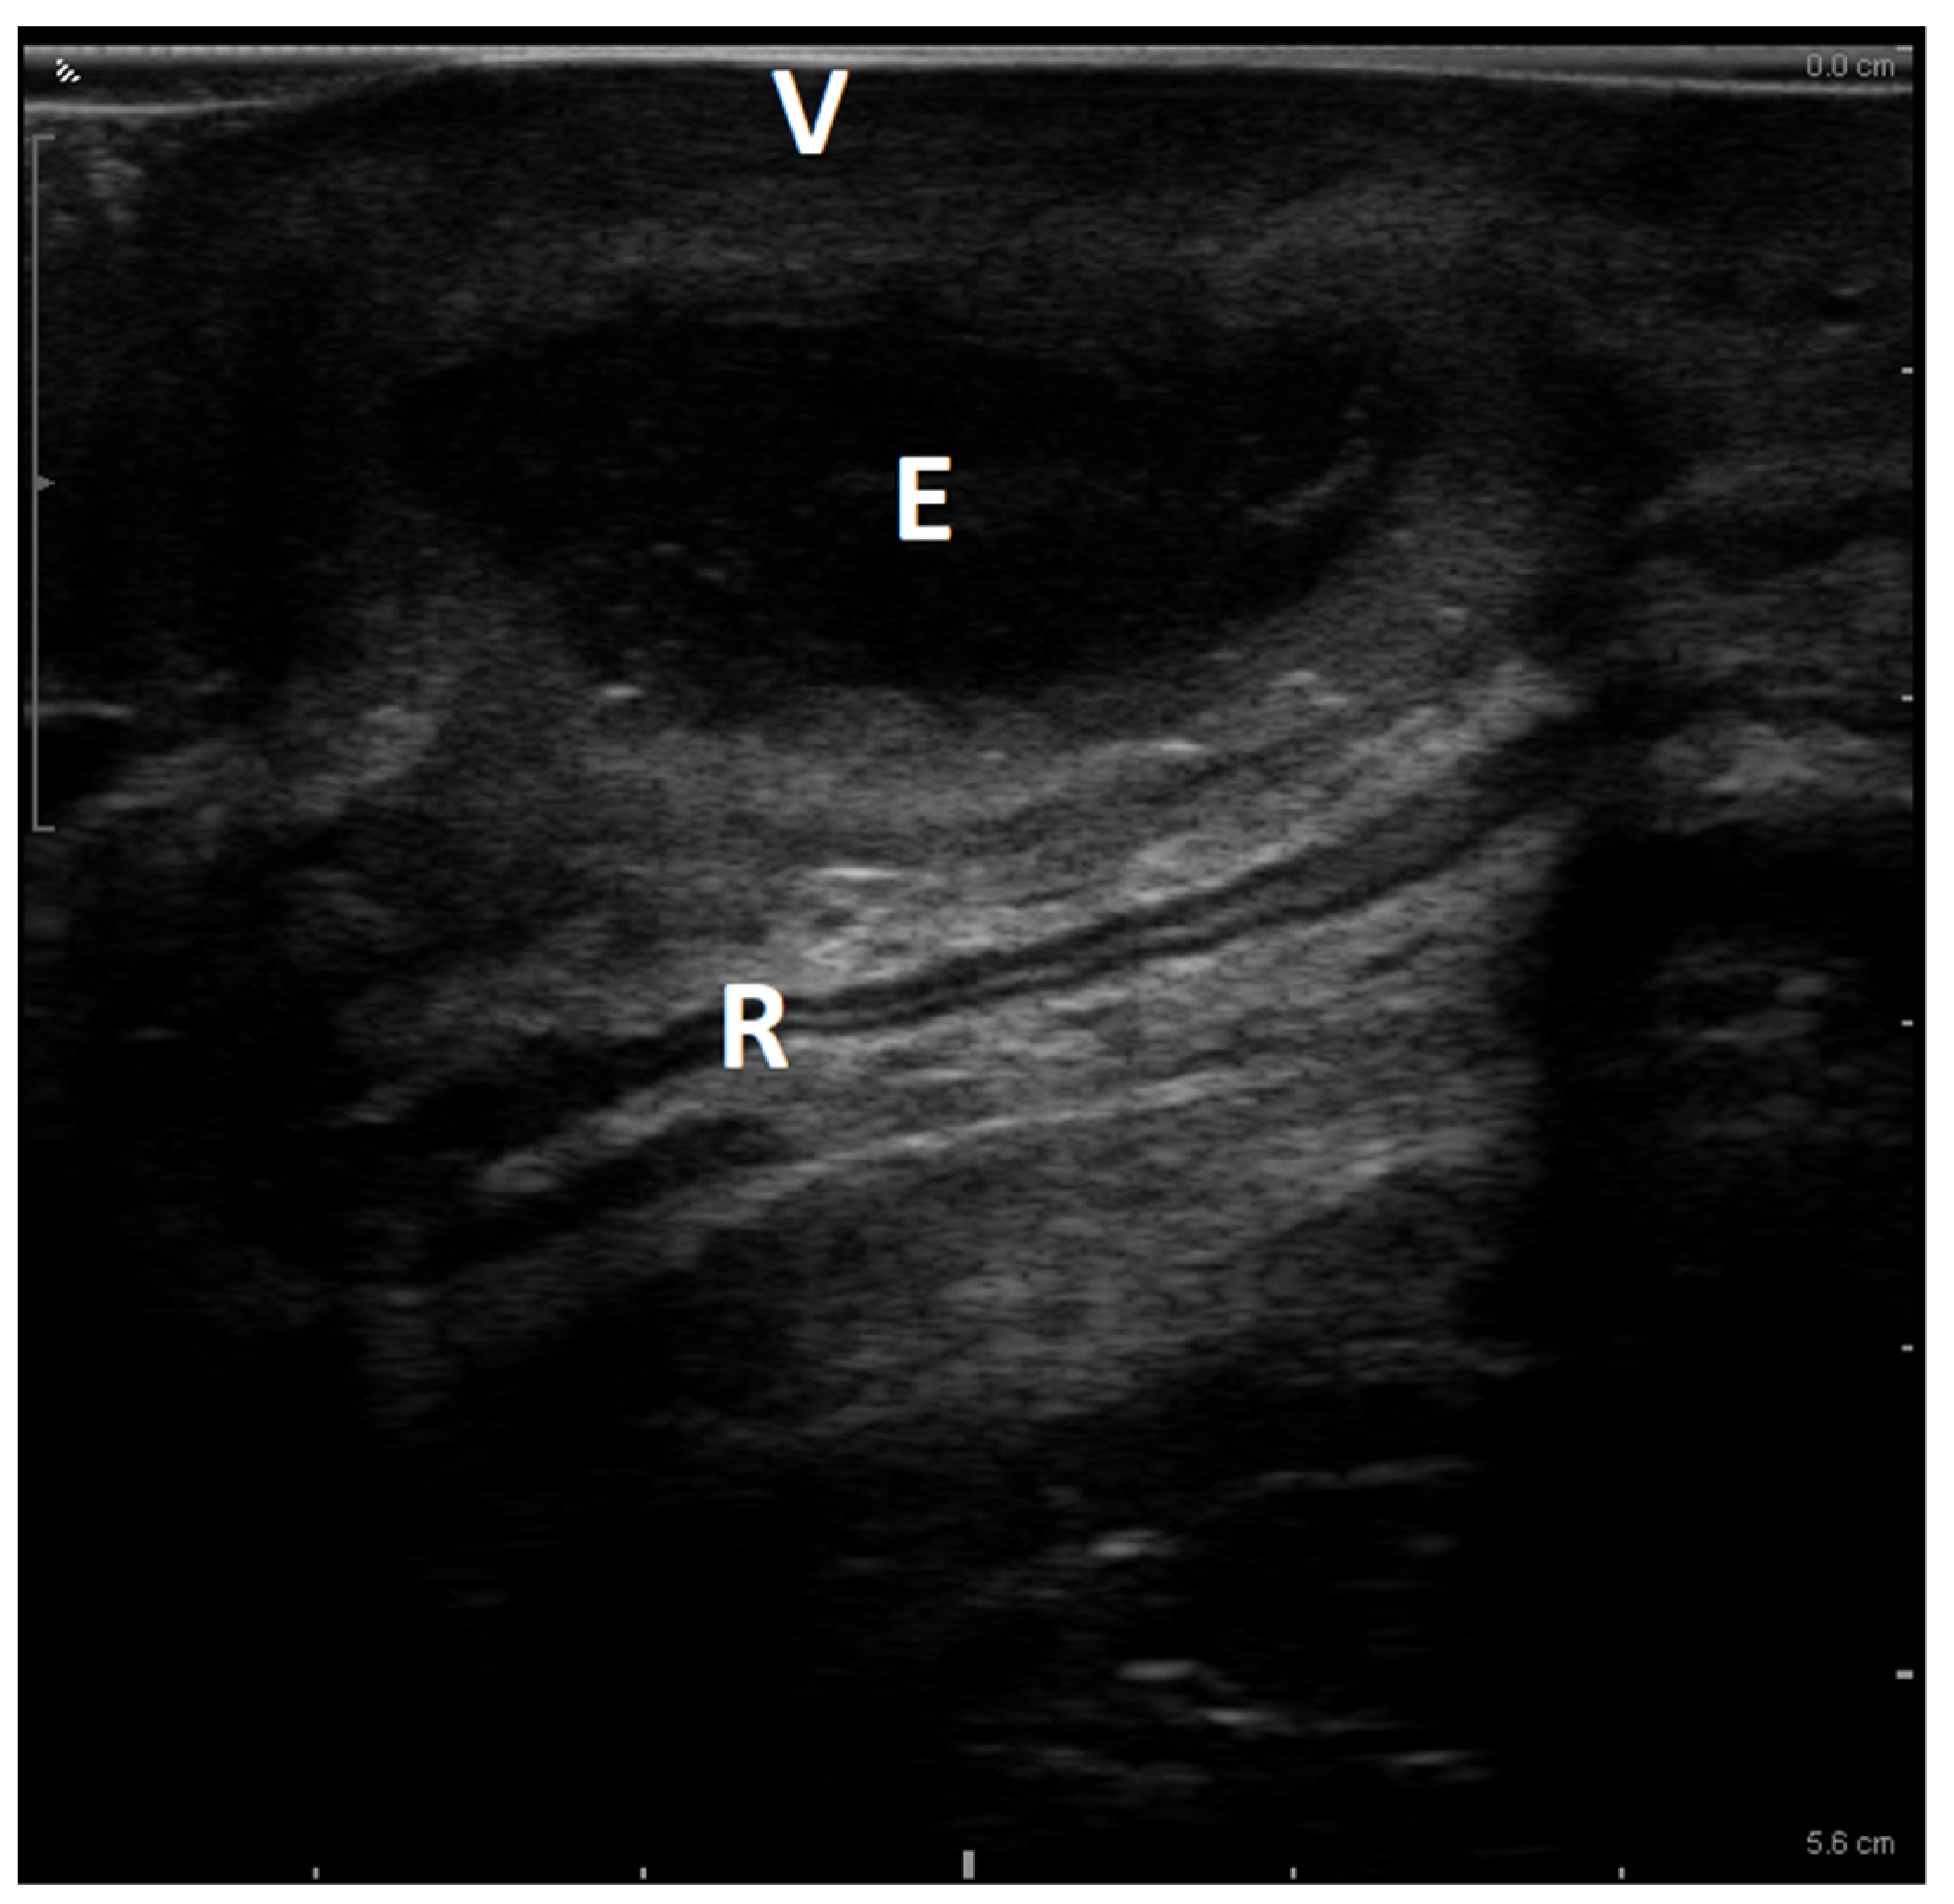

4.3. Imaging